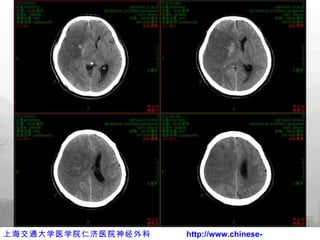

亚低温治疗

术后亚低温治疗